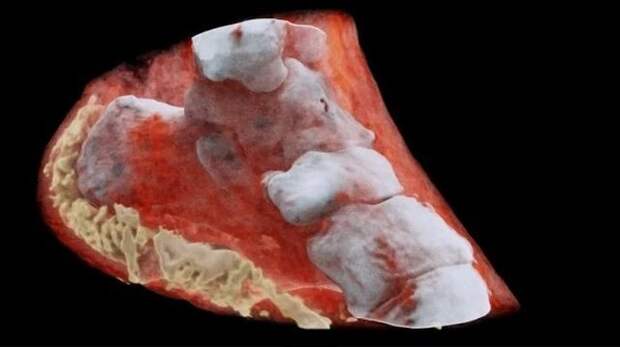

Лодыжка

Лодыжка  Рентген пациента, который весит 185 килограмм